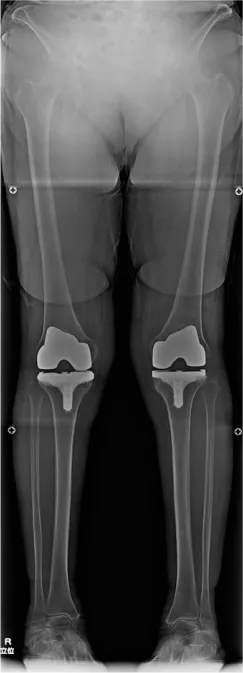

当院では、術後安定して歩ける膝、良好な機能獲得を目標に、個人個人の膝の形態に合わせたオーダーメイドの人工関節手術を行っております。骨の形は立体的に人それぞれ少しずつ異なっており、術後良好な機能を獲得するためには、それぞれの骨の形に合った手術を行うことが理想的です。

当院では術前のCT画像をコンピューターに取り込み、特別なソフトウエアを使用して、手術を受けられる方個々の骨の形に合うように手術前計画を立てています。

さらにその計画を元に正確な手術ができるよう、最新のARポータブルナビゲーションを使用して手術を行っております。

この手術法により、より正確な人工関節の設置が可能となり、より長期間の関節機能維持と膝の痛みの改善が期待されます。

しかも変形が高度な膝や再置換膝に対しても対応することができます。

• O脚膝 術前

• 人工関節置換術後